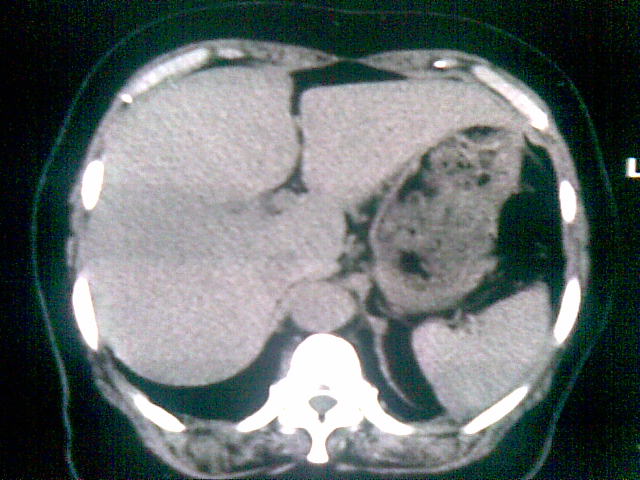

女 ,74岁,主诉食欲减退!上腹部痛,心慌!食管病变!请教ct会诊!

胃底贲门癌累及食管下段